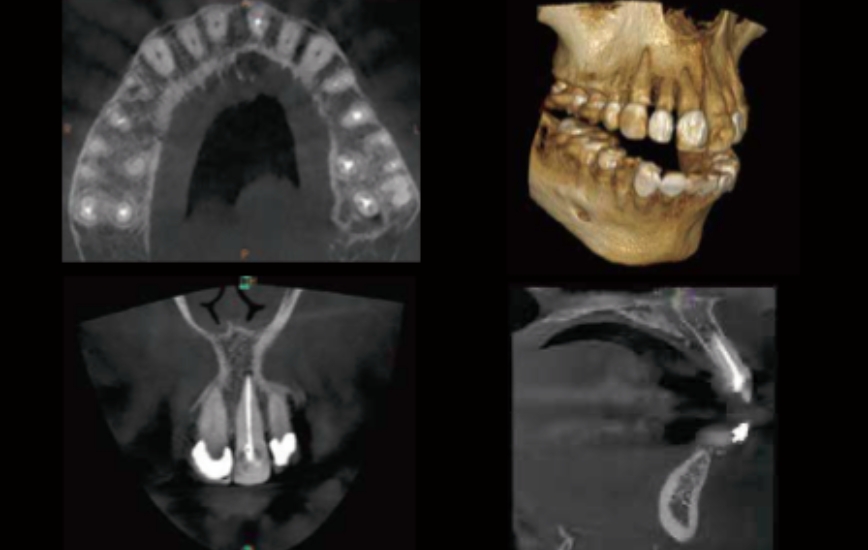

正確・的確な診療を行うための低線量歯科用CT、高度な感染対策を考えた滅菌機器から、3D口腔内スキャナーでの歯の型取りやマウスピース矯正、各チェアーに配置した口腔内カメラによる治療前後の比較など、患者様の負担の軽減と、治療の正確性を考えたを環境をご提供いたします。